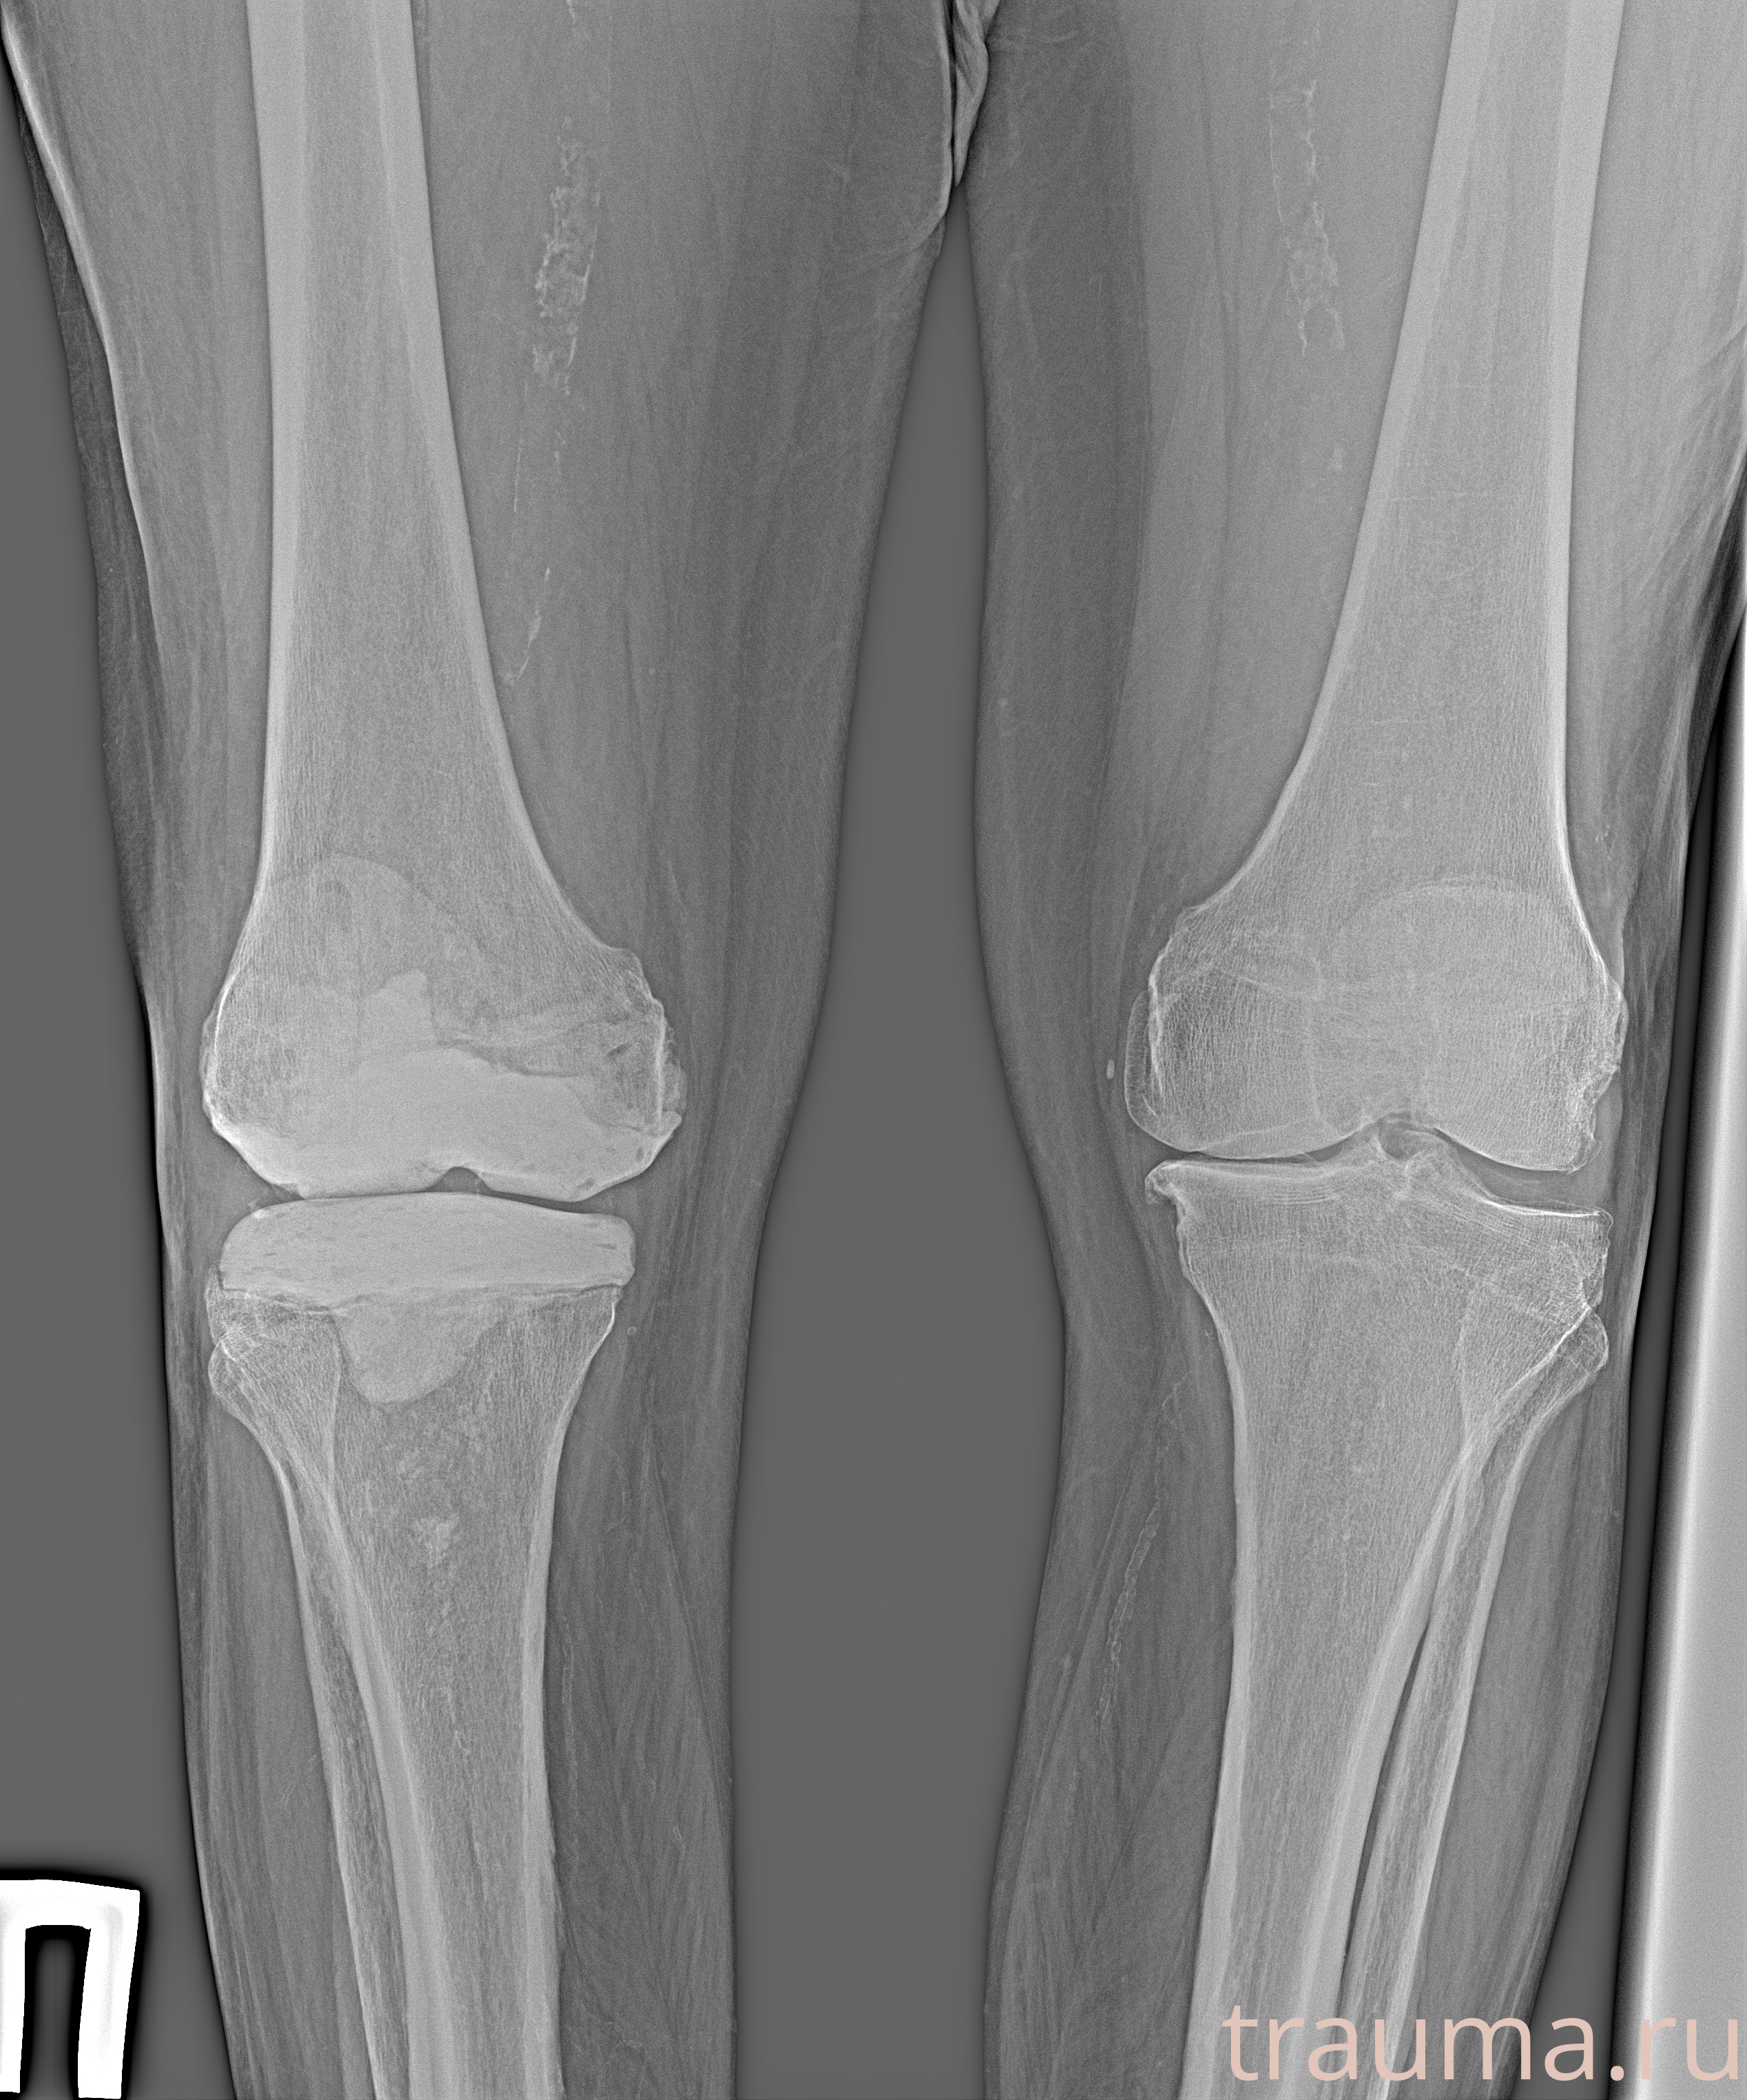

Рентгенограммы

Рентген на дому: по вашему адресу приезжает врач-рентгенолог, травматолог-ортопед с мобильным рентгеновским аппаратом, проводит диагностику травмы или заболевания, делает необходимые рентгенограммы, дает рекомендации по дальнейшему лечению. Получить качественные снимки в домашних условиях возможно благодаря уникальной методике, разработанной МосРентген Центром для института  Склифосовского